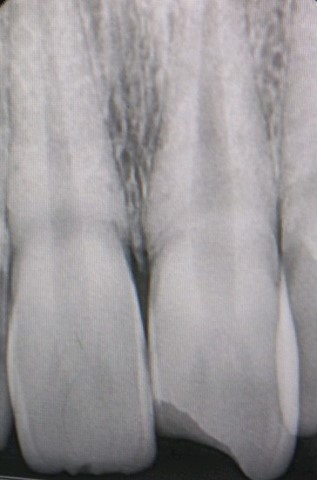

PRE - OP RADIOGRAPGH WORKING LENGTH MASTER CONE

COLD LATERAL COMPACTION OBTURATION